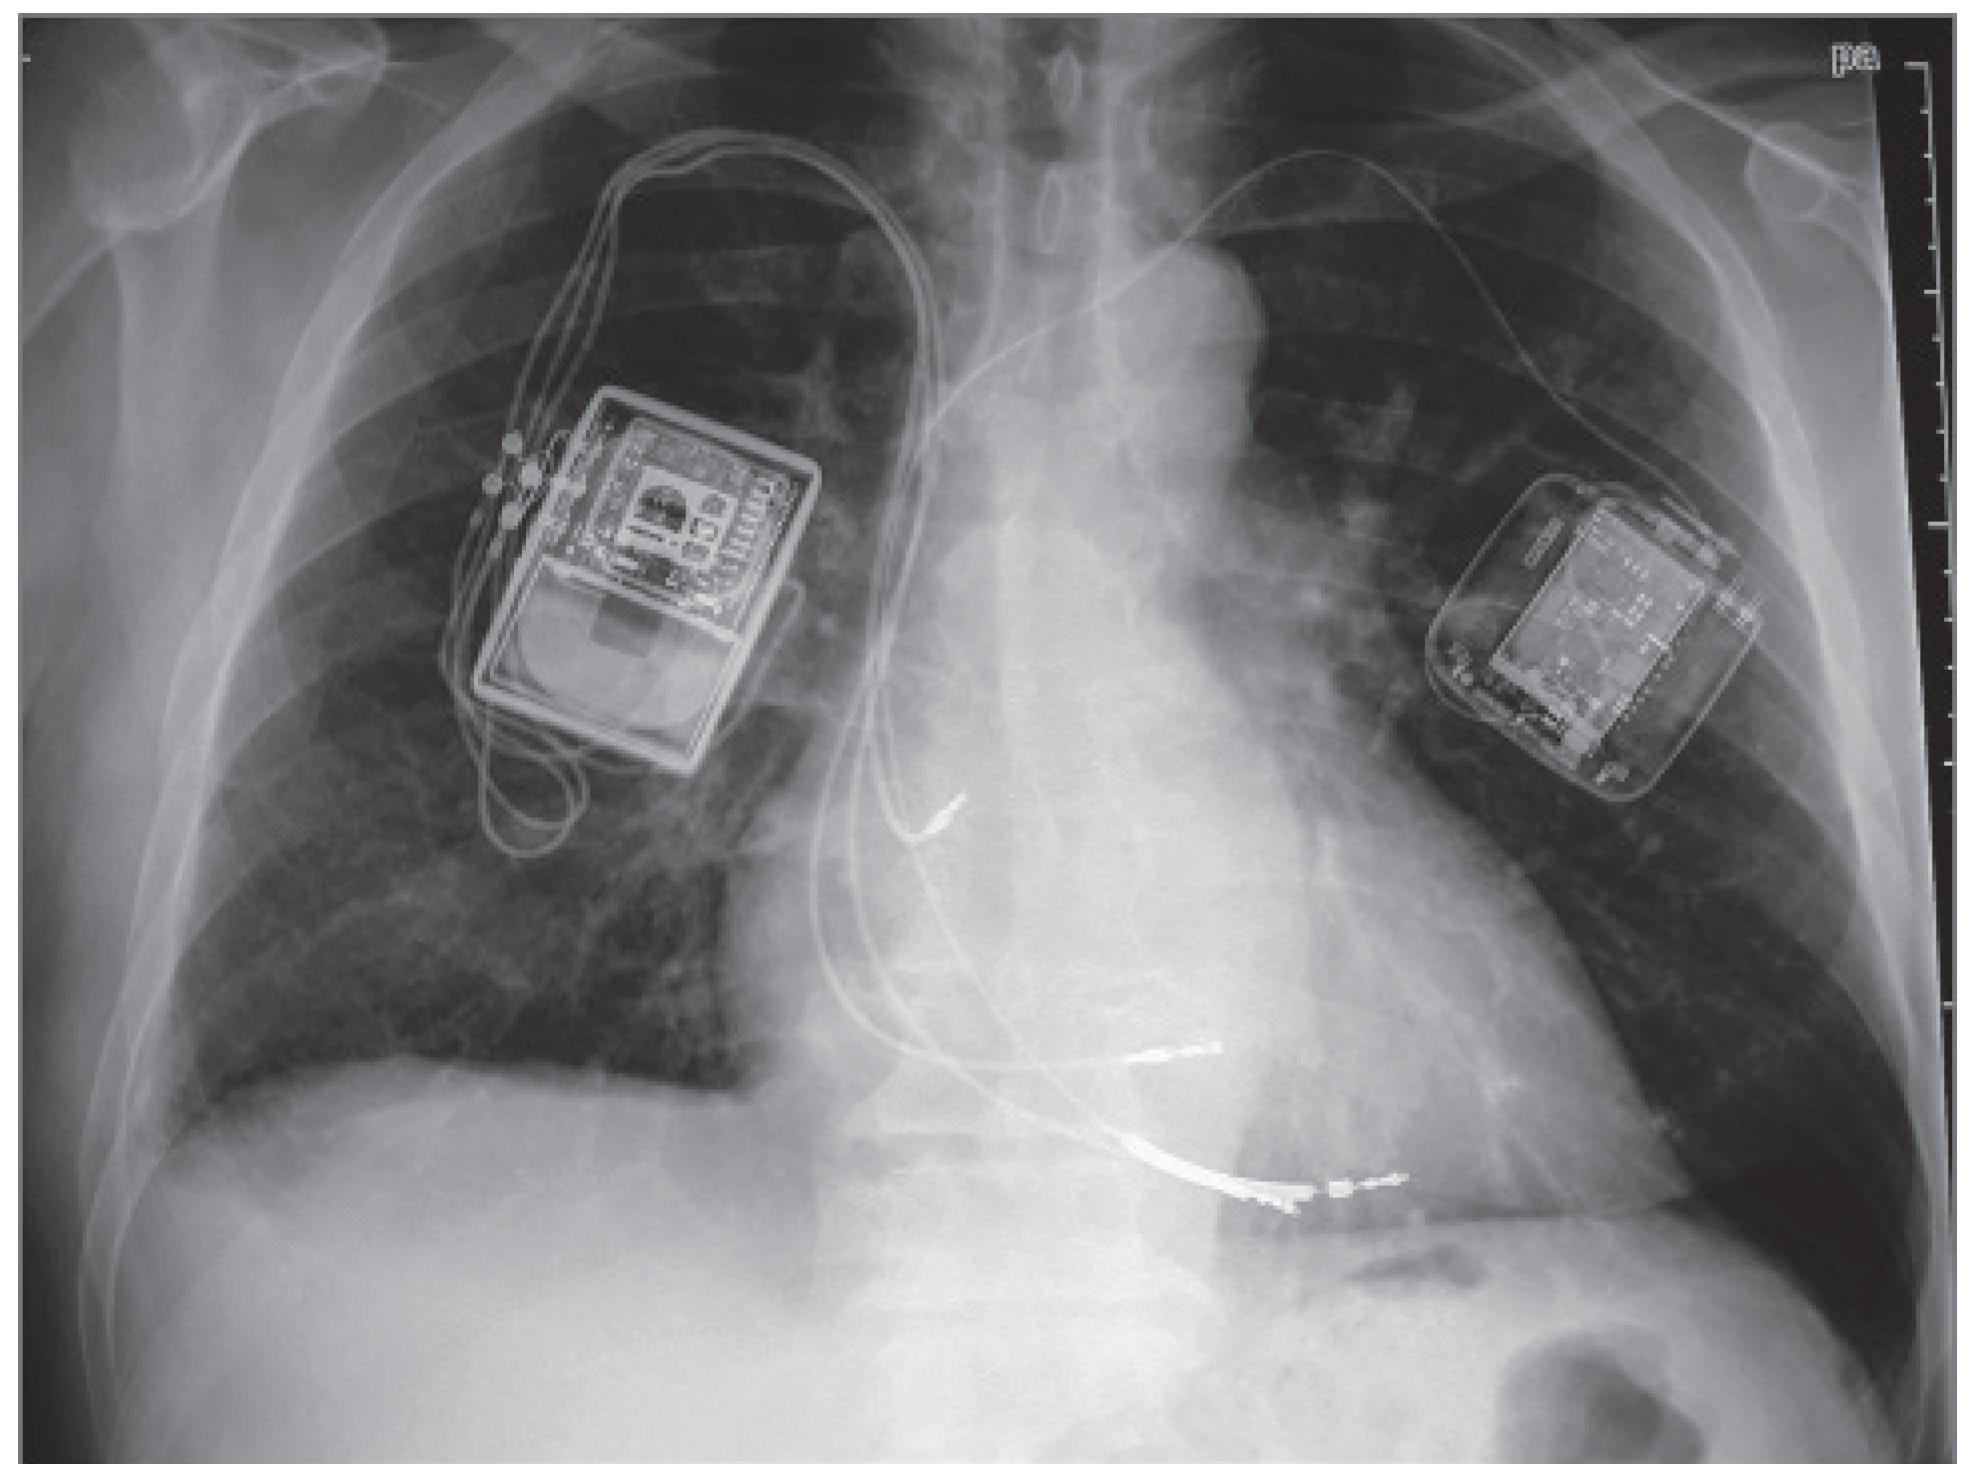

The device and implantation procedure